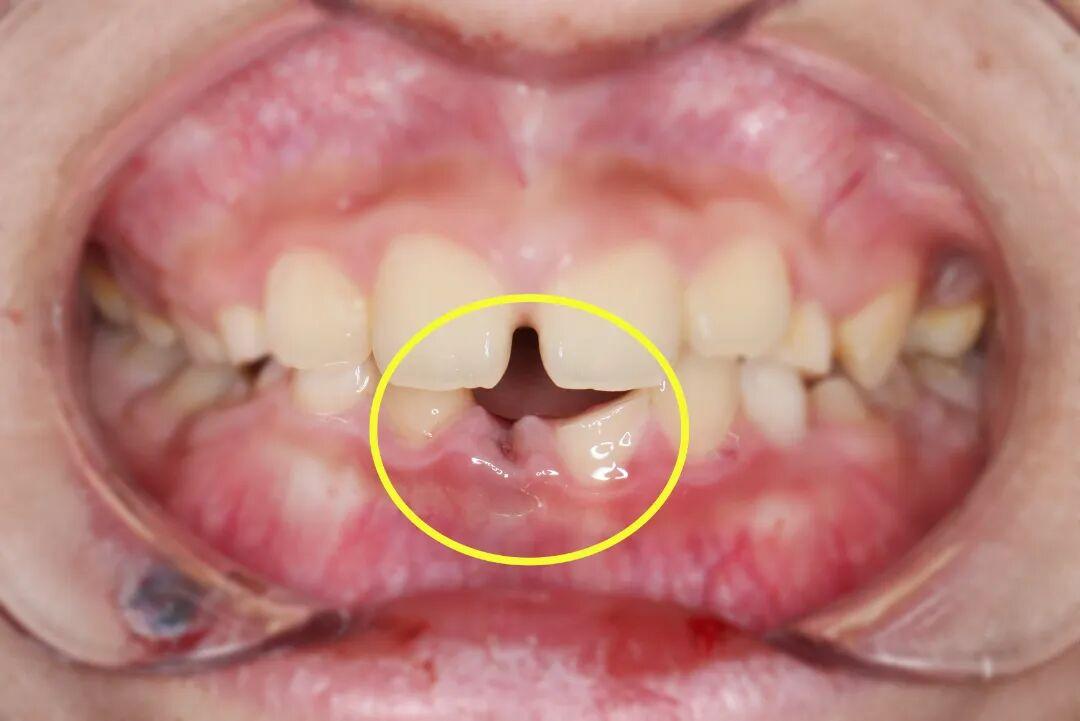

受伤的是两颗下前牙,其中一颗拦腰折断,另一颗不翼而飞。

“牙齿脱落时间越久,再植成功率越低,每一分钟都很关键!”口腔中心接诊后,立刻启动急救模式。口内检查和拍片检查发现,小千脱落的牙齿牙根完整,折断的牙齿已露髓(可见红点出血)。

针对双重损伤,杨主任制定了“拯救方案”:一方面要让脱落的牙齿“回家扎根”;另一方面要为“腰折” 的牙齿“挺起脊梁”。